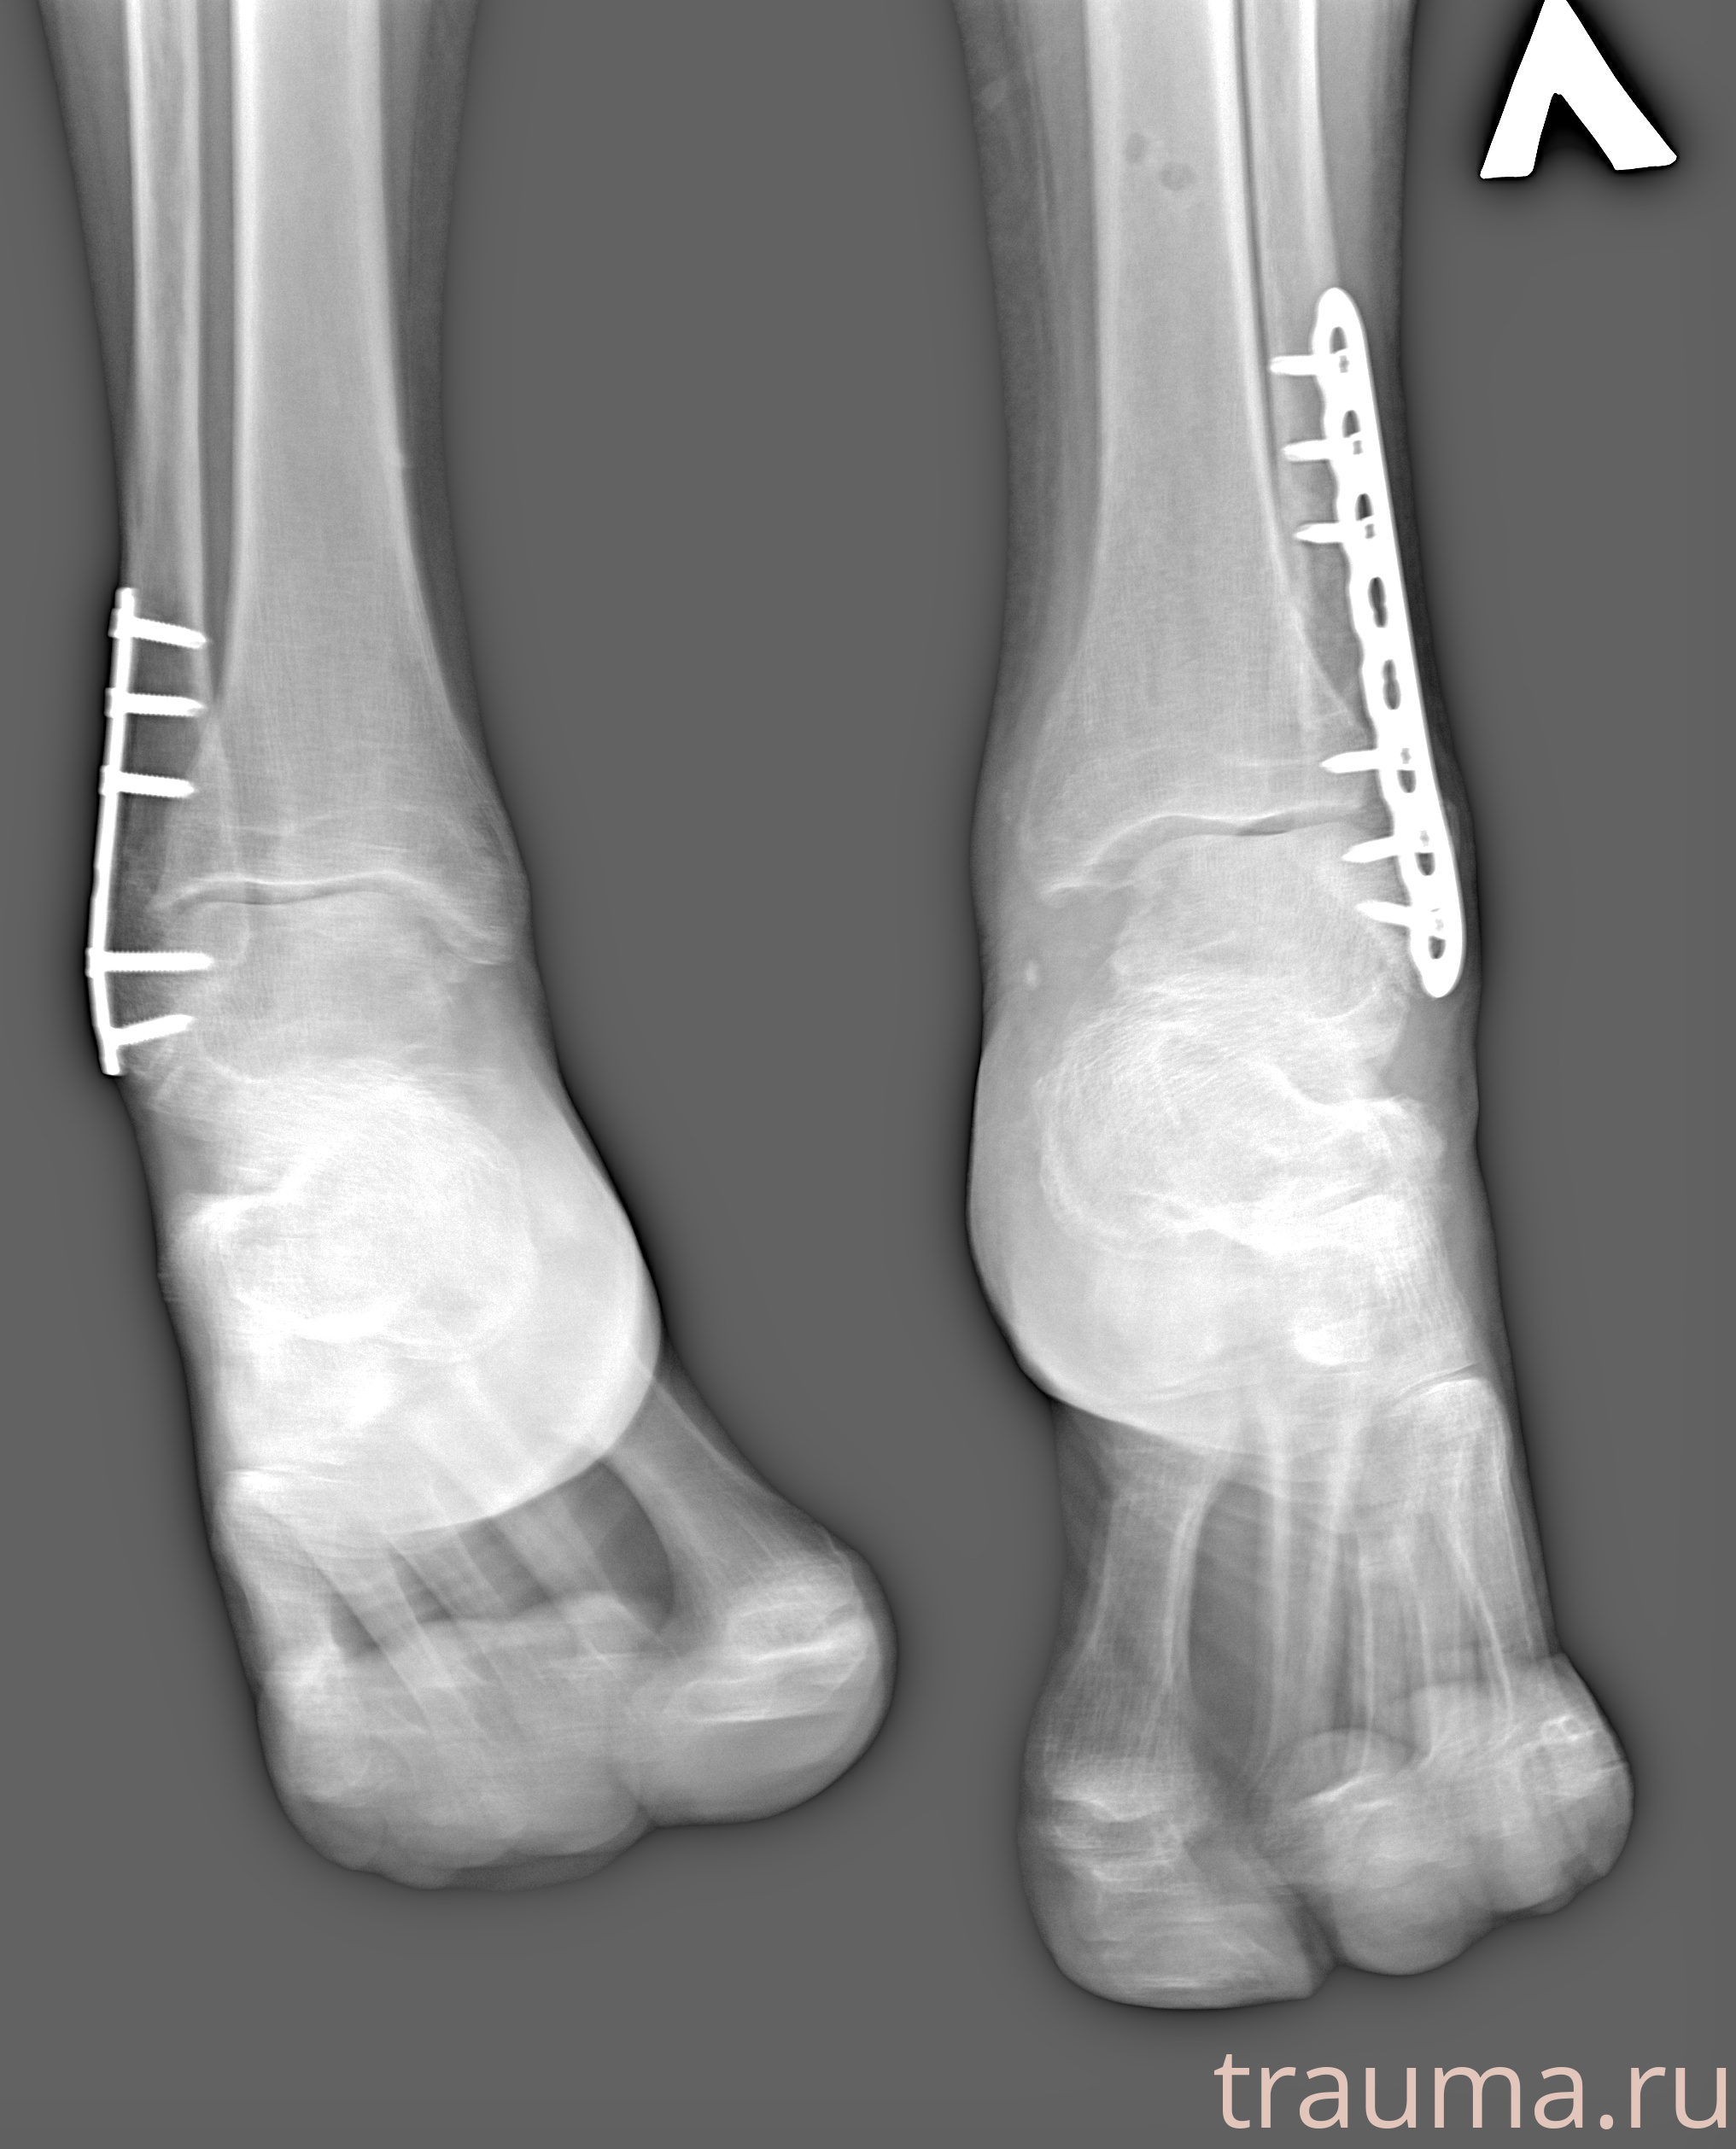

Рентгенограммы

Рентген на дому: по вашему адресу приезжает врач-рентгенолог, травматолог-ортопед с мобильным рентгеновским аппаратом, проводит диагностику травмы или заболевания, делает необходимые рентгенограммы, дает рекомендации по дальнейшему лечению. Получить качественные снимки в домашних условиях возможно благодаря уникальной методике, разработанной МосРентген Центром для института  Склифосовского